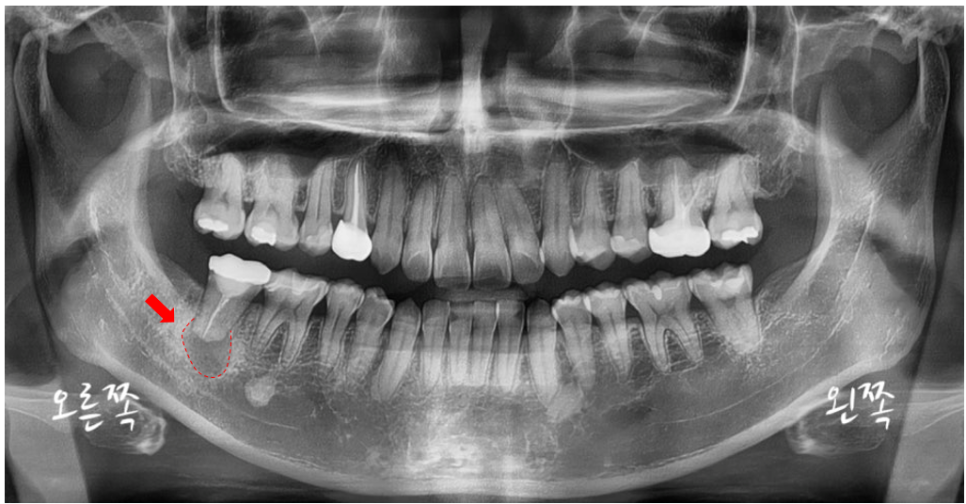

같은 부위의 CT 사진입니다.

아래에 보이는 X-ray에서 빨간색으로 표시된 부위는,

앞서 파노라마 X-ray에서 보였던 검은 음영 부위입니다.

염증으로 인해 치조골(잇몸뼈)이 녹아 생긴 공간입니다.

그리고 파란색으로 표시된 부위는

우리가 흔히 ‘하치조신경’이라고 부르는

inferior alveolar nerve (IAN)입니다.

이 신경은 아래턱의 감각을 담당하는 중요한 구조인데요,

보통은 단단한 뼈 속에 안전하게 보호되어 있습니다.

그런데, 염증이 심해지면

이 신경을 직접 압박하거나,

신경을 감싸고 있는 뼈 자체를 녹여버리는 경우도 생깁니다.

그렇게 되면 마취가 풀리지 않는 듯한 먹먹함이나 감각 이상이 생기기도 합니다.

이 환자분의 경우, 치아를 살릴 수 있는 가능성을 고려해

‘치아 재식술’을 진행하기로 했습니다.